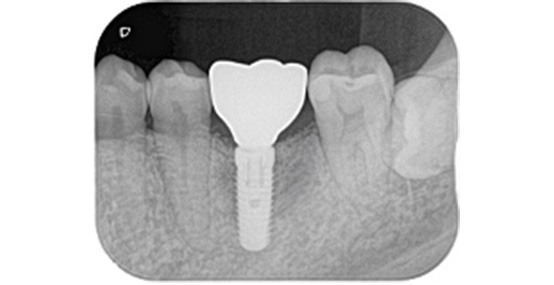

手術後は大きなトラブルもなく、しっかり咬めて、違和感がない状態で、現在も良好に経過しています。

左:最終的な被せものの装着時の状態

中:インプラントのホール(穴)を樹脂で封鎖した後

右:装着後の状態のレントゲン写真です

上:最終的な被せものの装着時の状態

下:装着後の状態のレントゲン写真です

インプラントの植立位置を工夫することによって左下の被せものの厚みが確保され、被せものが割れにくい構造にすることができました。

術前の被せものの厚みが薄いという問題点も骨の高さ及びインプラント体を入れる深さを調整することにより十分な被せものの厚みが確保できています。